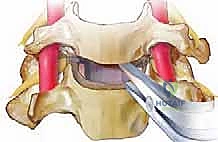

الخطوة 5: تخفيف الضغط العصبي (Decompression)

هذه هي المرحلة الأهم والأكثر حساسية. يقوم الجراح بإزالة أي نتوءات عظمية (Osteophytes) أو أجزاء من الغضروف الممزق التي تضغط على الأعصاب الشوكية أو الحبل الشوكي، مما يعيد للقناة الشوكية اتساعها الطبيعي.